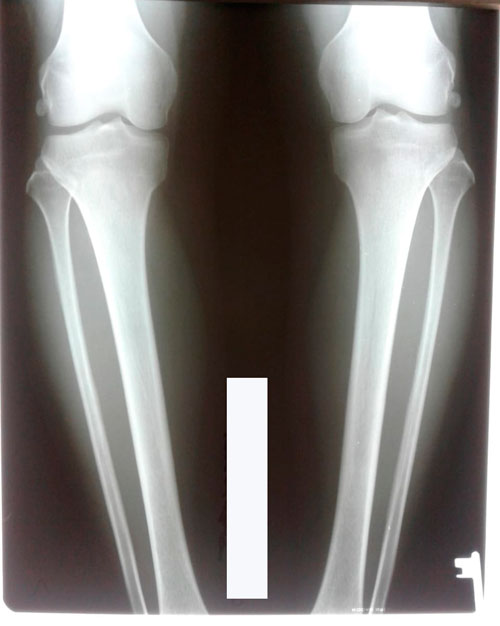

Исходник - 36 лет. Актау.

Дата операции - 19.06.2018г.

Дата снятия аппаратов 19.09.2018г.

Срок лечения 90 дней.